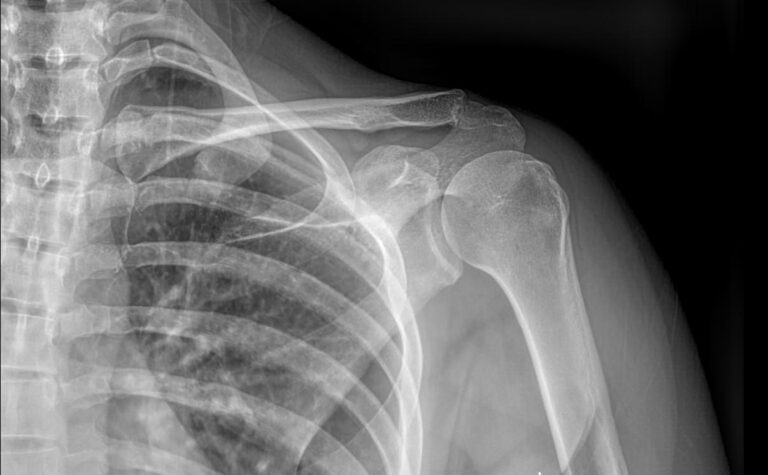

На снимке видны:

• Рукоятка грудины ― ее верхняя часть;

• Грудинные концы ключиц ― в норме или перелом;

• Суставные щели между грудиной и ключицами, их состояние, говорящее о хронических воспалениях;

• Соответствие суставных поверхностей ― норма, подвывих, вывих;

• Новообразования.